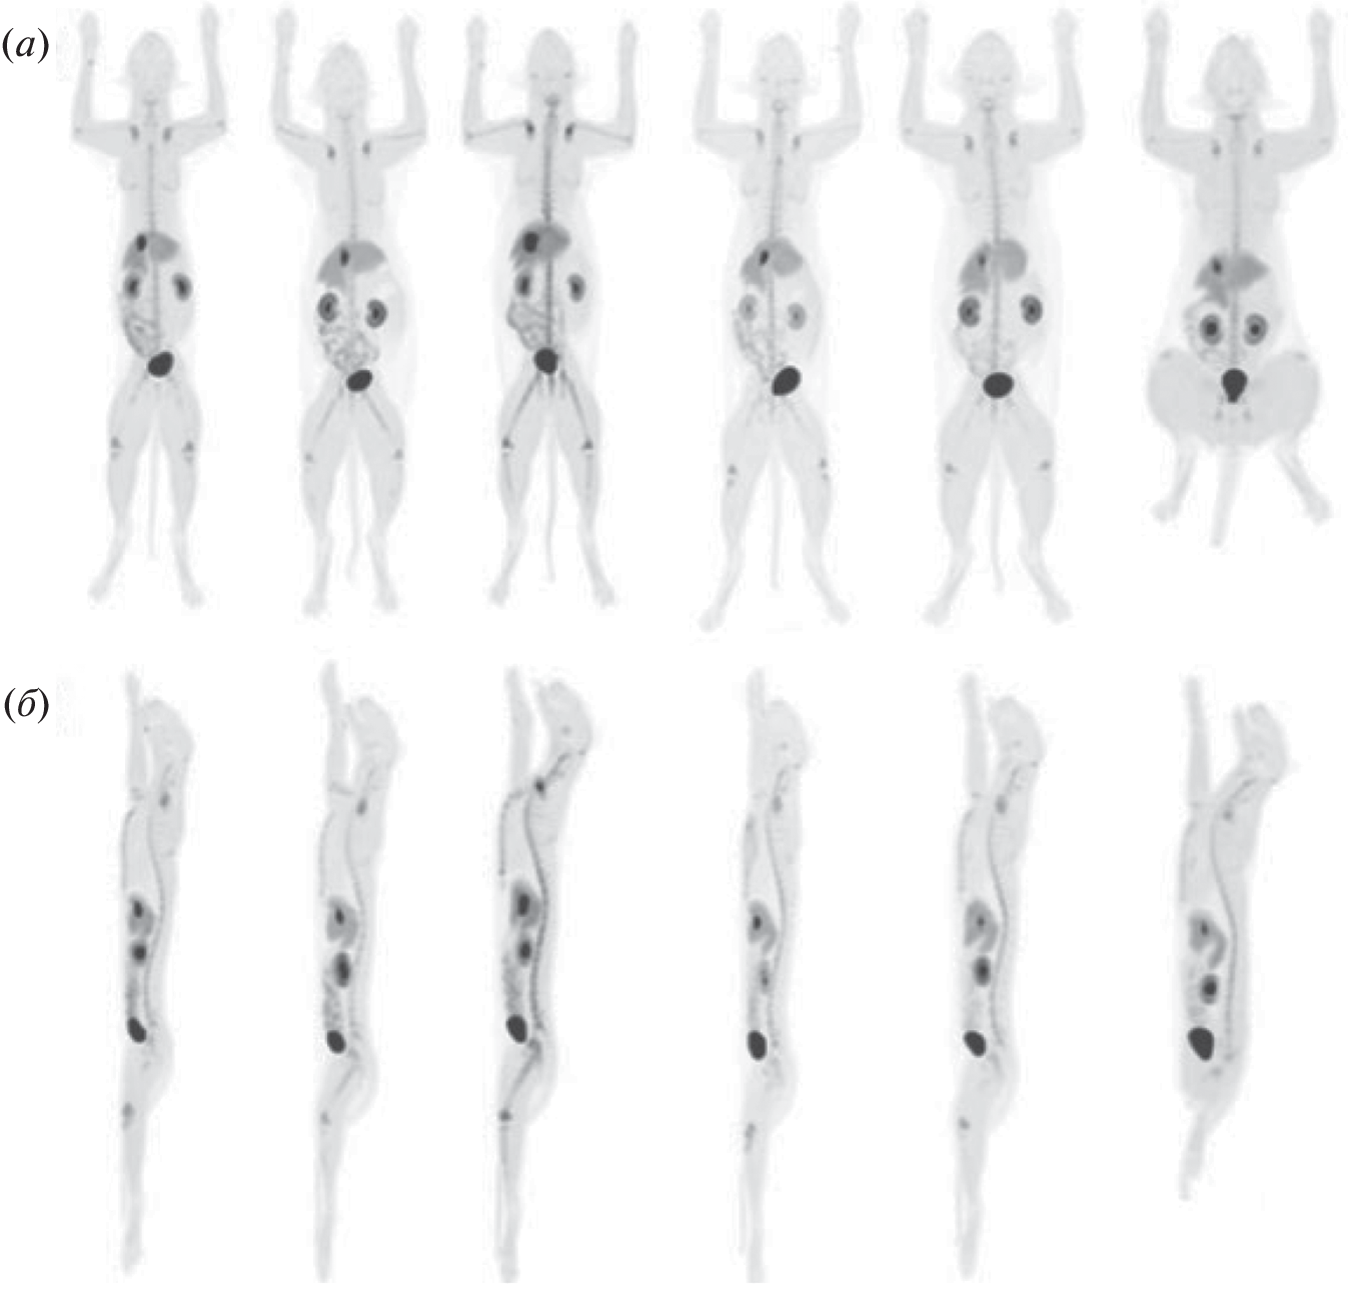

To date, the most common drug for the diagnosis of cancer tumors is [18F]-fluorodeoxyglucose, an radiopharmaceuticals for positron emission tomography diagnostics using the fact of increased glucose metabolism by cancer cells. At the same time, there are a number of cases where an approach based on glucose derivatives is not applicable. In many cases, inflammation or other benign processes are indistinguishable from tumor formations. For such cases of non-specificity of oncologies to glucose (not only tumor cells, but also healthy cells actively consume [18F]-fluorodeoxyglucose), the use of other metabolic pathways is required, which, in the case of a specific tumor in this organ, will be specific to the radiopharmaceuticals used.